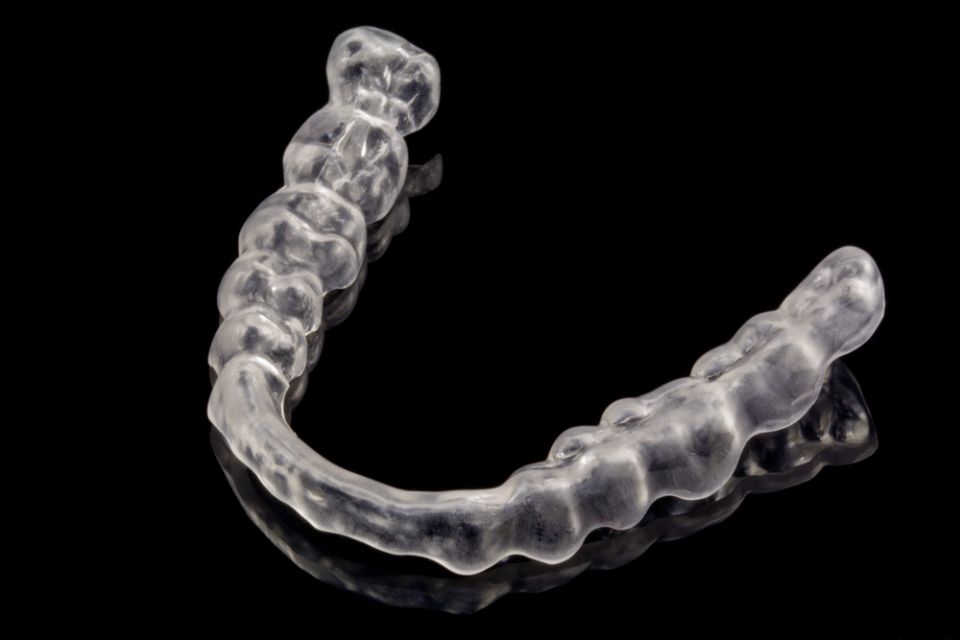

. Invisaling®

L'Invisaling és la tècnica d'ortodòncia en què es fan servir alineadors transparents. La tecnologia avançada daquest sistema es basa en imatges computaritzades en 3D on es visualitza la imatge de les dents des de linici del tractament fins al resultat final. Els alienadors són totalment personalitzats.